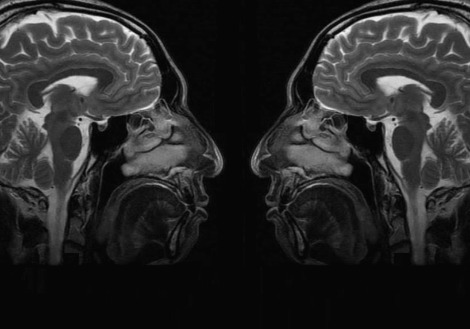

뇌 앞쪽 뒷쪽.jpg 마주보는 뇌

우리 뇌는 크게 나누면 앞쪽 뇌와 뒷쪽 뇌가 있다. 뒷쪽 뇌는 주로 외부에서 들어오는 감각정보를 받아들이고 앞쪽뇌는 뒷쪽 뇌에서 들어오는 정보를 해석하고 행동하고 조절한다. 감각피질(뒷쪽)과 운동피질(앞쪽)을 나누는 중심회(central sulcus)를 중심으로 앞쪽과 뒷쪽을 나누는데, 전두엽이 앞쪽에 있고 이 영역은 감각이나 감정을 해석하고 조절하고 억제한다. 시각, 청각, 촉각 등의 감각들은 뒷쪽뇌가 담당한다.